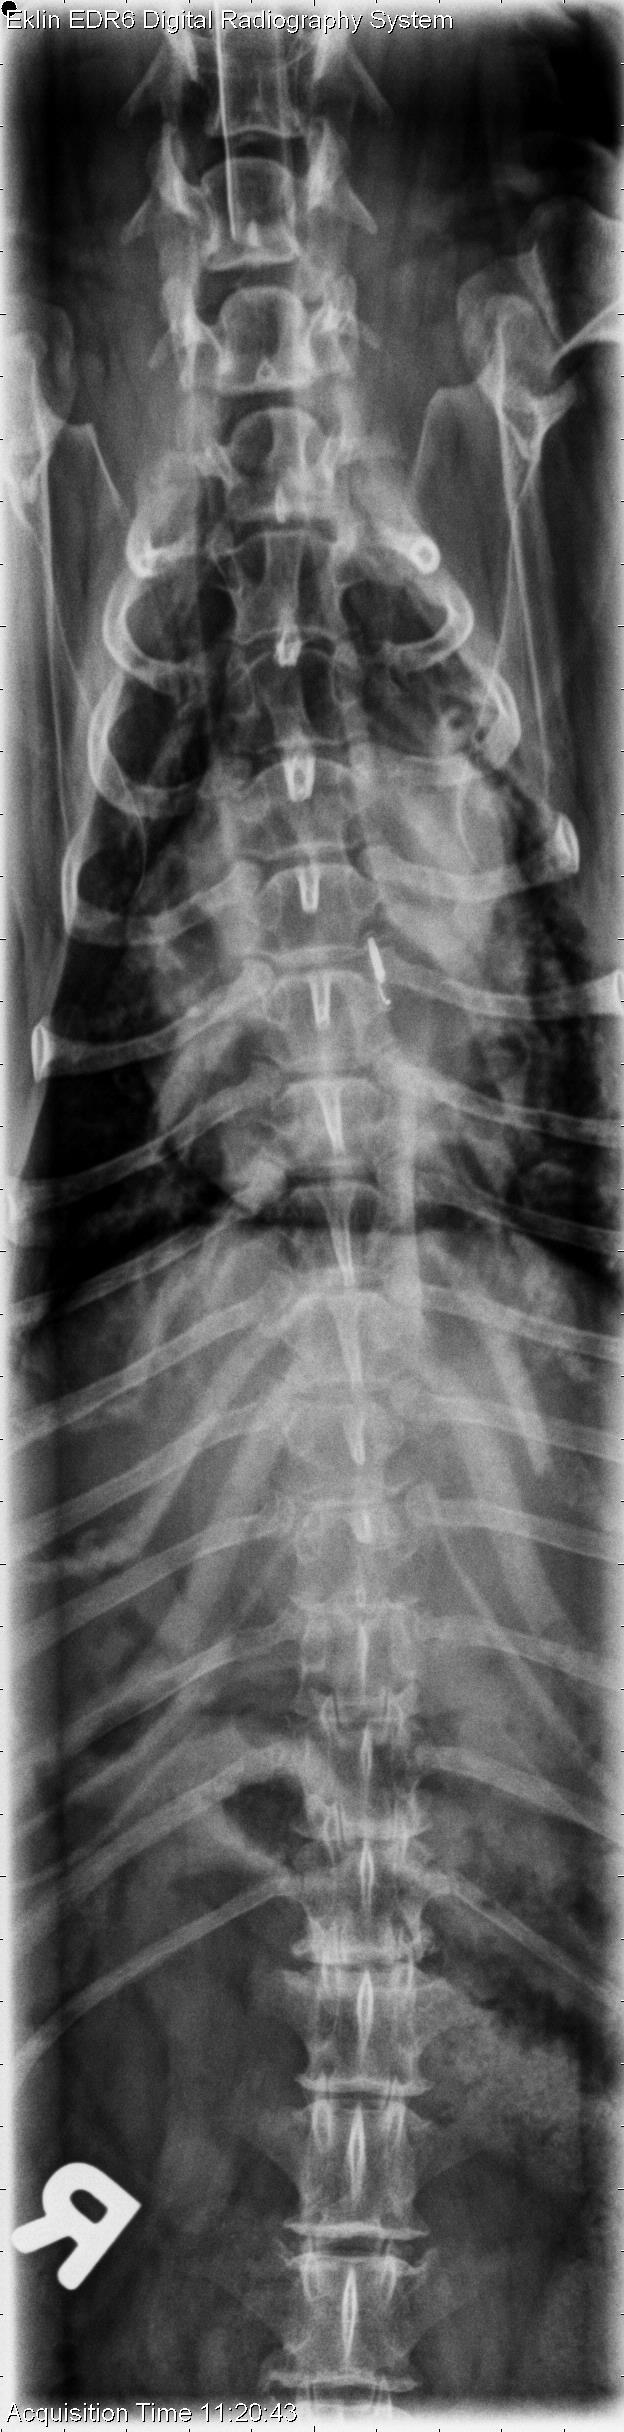

This week’s case is a 15-year-old female neutered Dachshund with several weeks history of non-ambulatory paraparesis. The tentative diagnosis is T3-L3 myelopathy. What are your findings?

On radiographs of the spine, there is scleroisis of the L6 vertebra most apparent on the lateral projection. On the ventrodorsal projection, there is loss of the cortical bone of the lamina at this level. The intervertebral foramen at L6-7 is irregular and enlarged. There is multifocal intervertebral disc space narrowing including T12-13, T13-L1, and L3-4, as well as spondylosis deformans throughout the spine.

The lysis and sclerosis of the L6 vertebra are consistent with an aggressive lesion, most likely neoplasia.

An MRI was performed, demonstrating a compressive mass in the L5-L7 region with spinal cord compression. Fine needle aspirate revealed malignant neoplasia, most likely sarcoma.